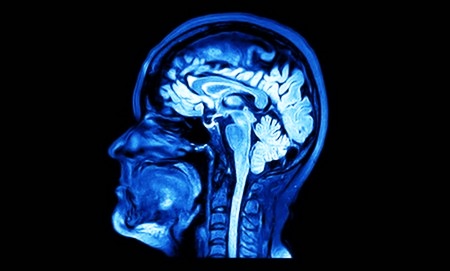

МРТ является неинвазивным обследованием с использованием высокочастотного магнитного поля, основанным на получении снимка с детальным изображением мозга. При МРТ головного мозга рентген не применяется. Данная методика помогает выявить опухоли, аневризмы, патологии в сосудистой и нервной системе.

Помимо этого, исследование помогает определить степень активности коры. МРТ головного мозга может проводиться с введением контрастного вещества и без него. Контраст увеличивает отличие между тканями, что дает возможность выявить даже мельчайшие патологии. Его используют достаточно редко из-за риска возникновения аллергических реакций.